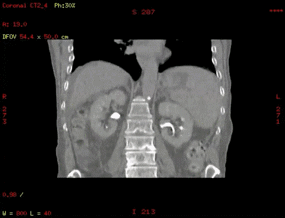

于是,我可以走进更多的科室,当然我的老家影像科,我也是常回来看看,我可以达到和诊断CT一样的空间分辨率和密度分辨率,因为我有一颗强劲的心脏,一天轻松完成百余例患者扫描。

在放射治疗科,我可以进行放疗患者CT定位扫描,我可以不依靠第三方厂家,自己做四维呼吸门控扫描,我可以自动去除患者金属伪影,我的老搭档SIM兄弟可以自动勾画正常器官外轮廓,支持在四维CT图像上实时定义修改结构,可以存储为RT DICOM格式发送给TPS。